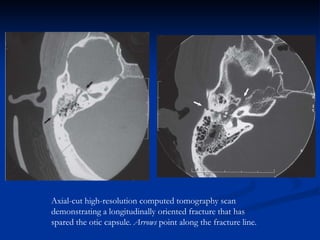

Axial-cut high-resolution computed tomography scan

demonstrating a transverse-oriented fracture that

resulted from a gunshot injury and disrupted the otic

capsule. The arrow points to the fracture line.

demonstrating a longitudinally oriented fracture that has

spared the otic capsule. Arrows point along the fracture line.